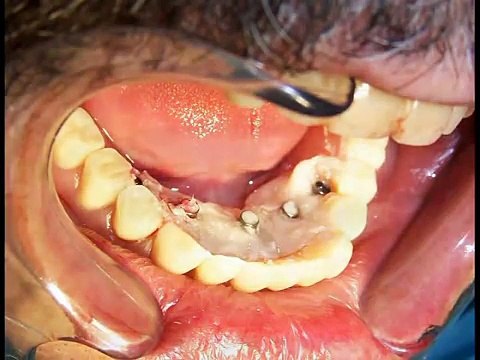

Implantes com carga imediata

Uploaded: September 11, 2015 Views: 3